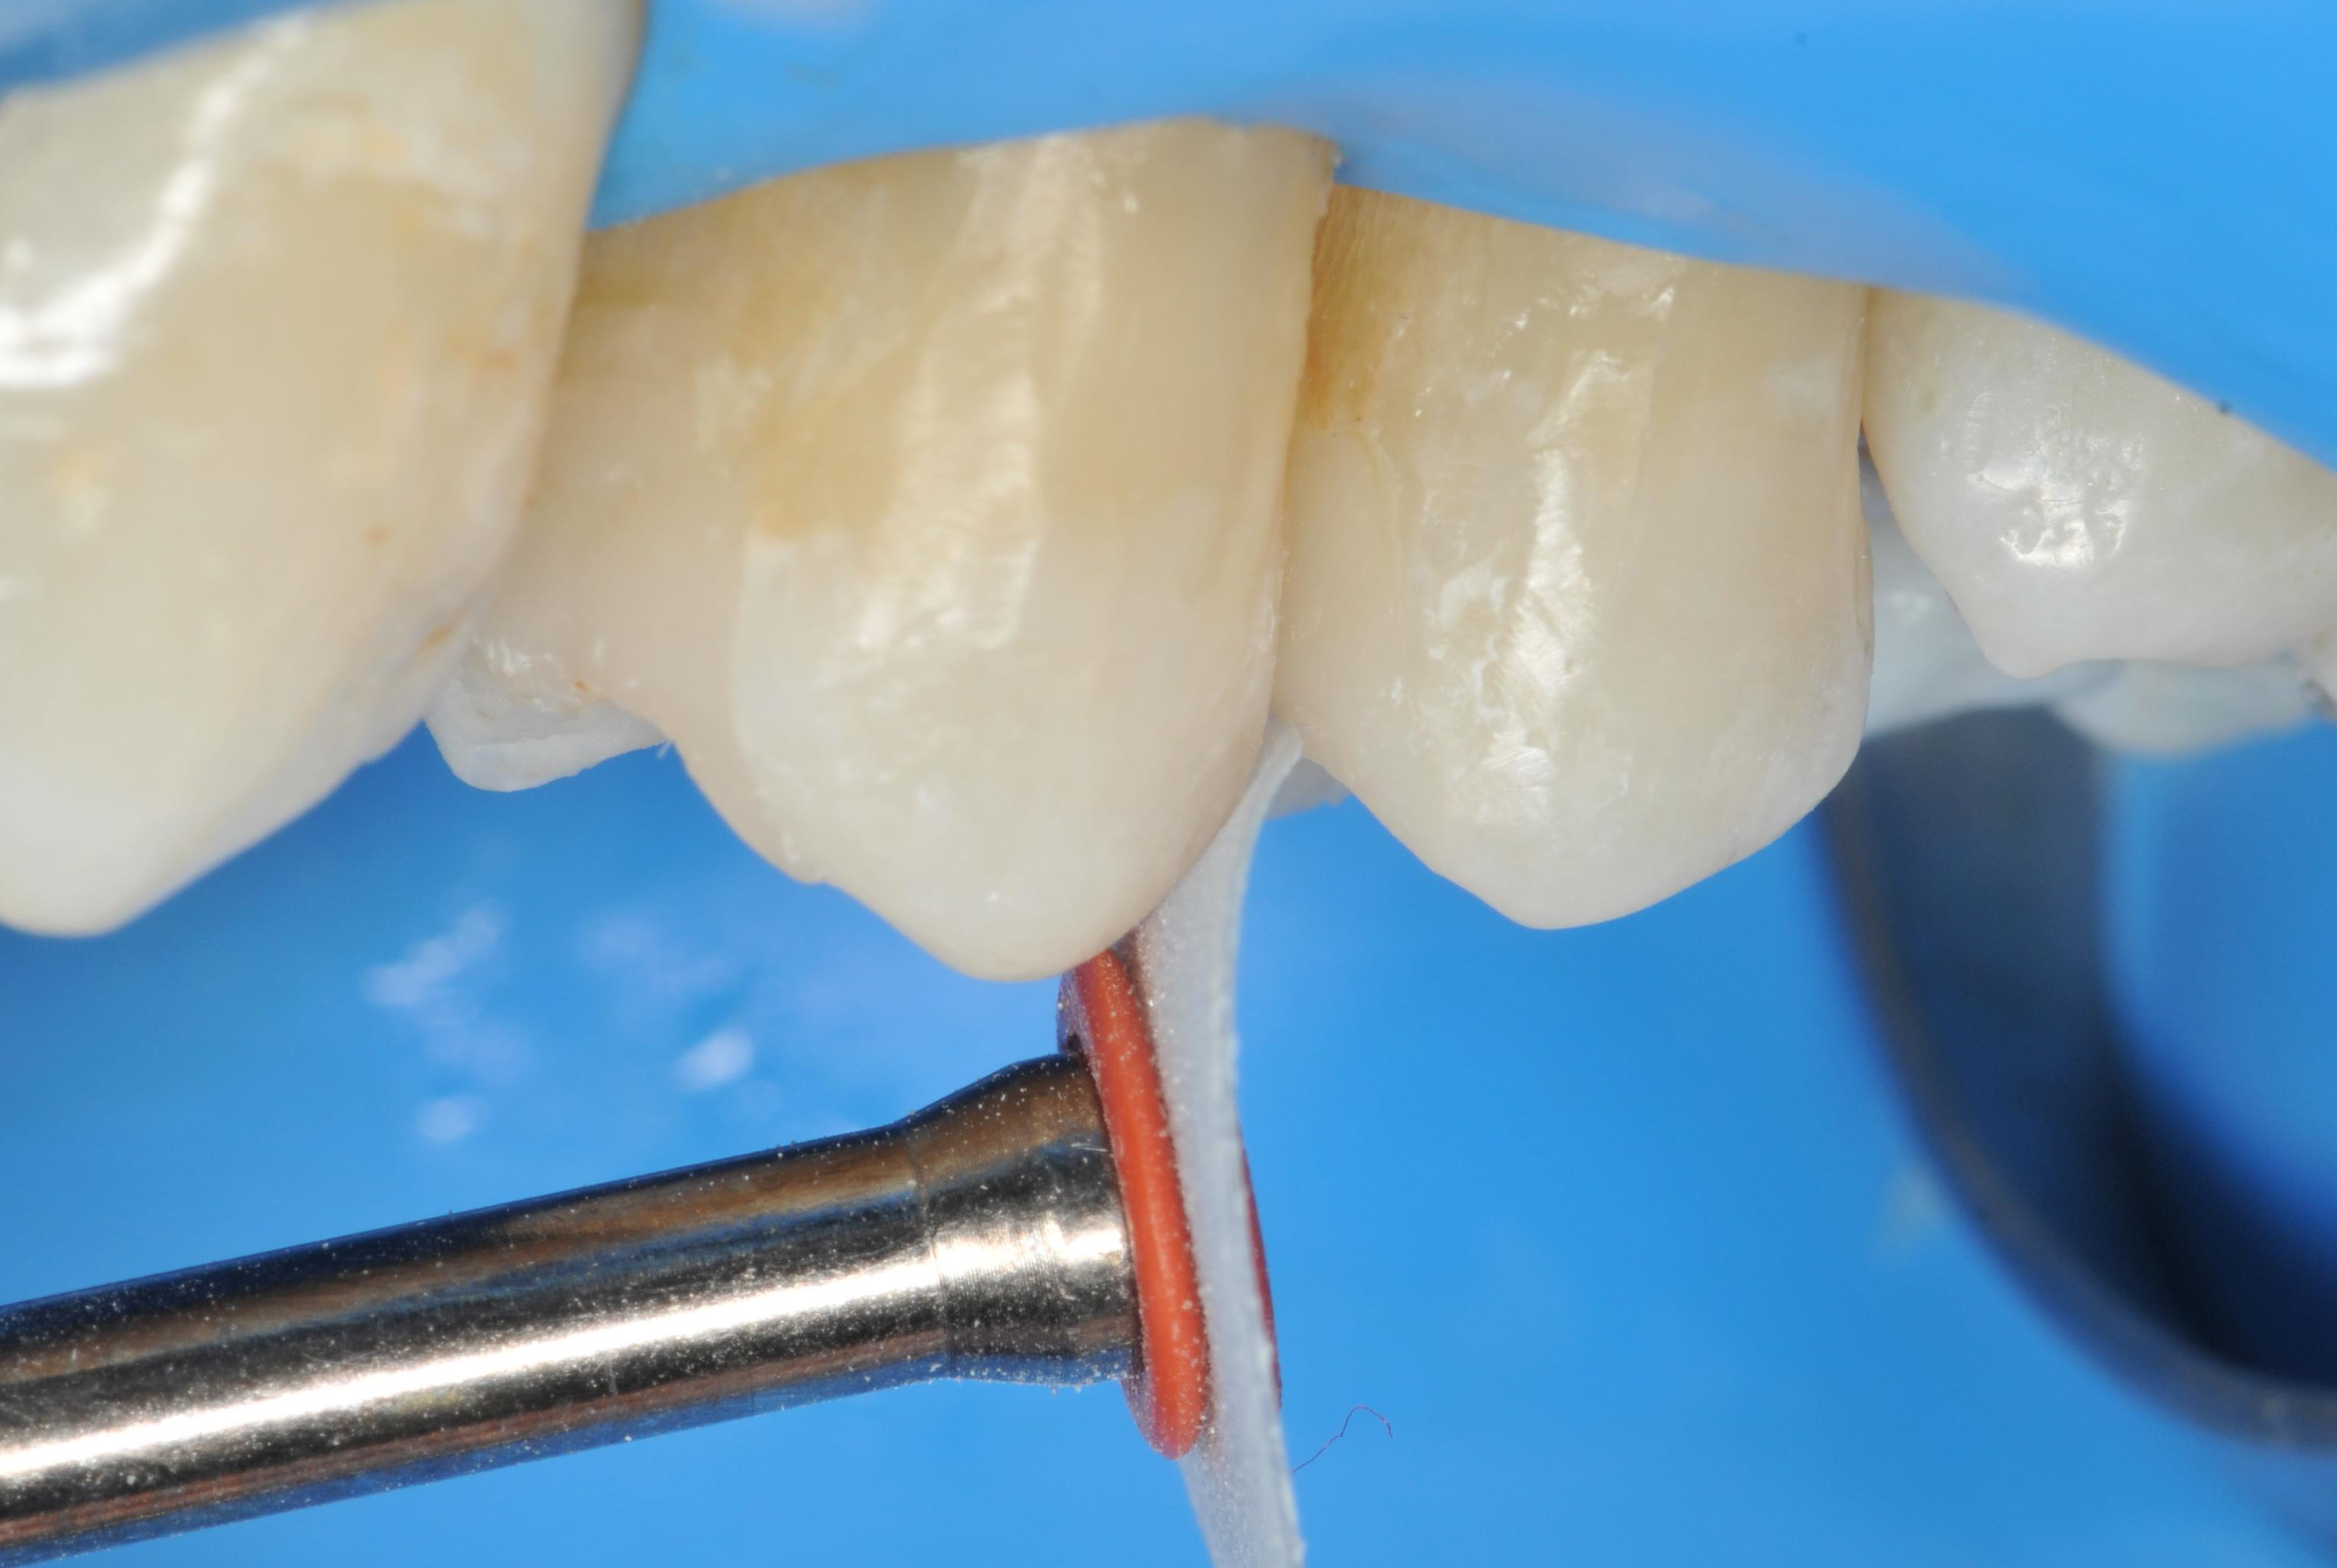

Po przygotowaniu ubytków, do każdego z nich umieszczono dwie sekcyjne matryce, aby uzyskać jak najściślejszy kontakt, a następnie zabezpieczono je pomarańczowym drewnianym klinem (ryc. 3).

Następnie odłamano zewnętrzną część klina, tak aby w strefie międzyzębowej pozostała tylko jego część (ryc. 4).